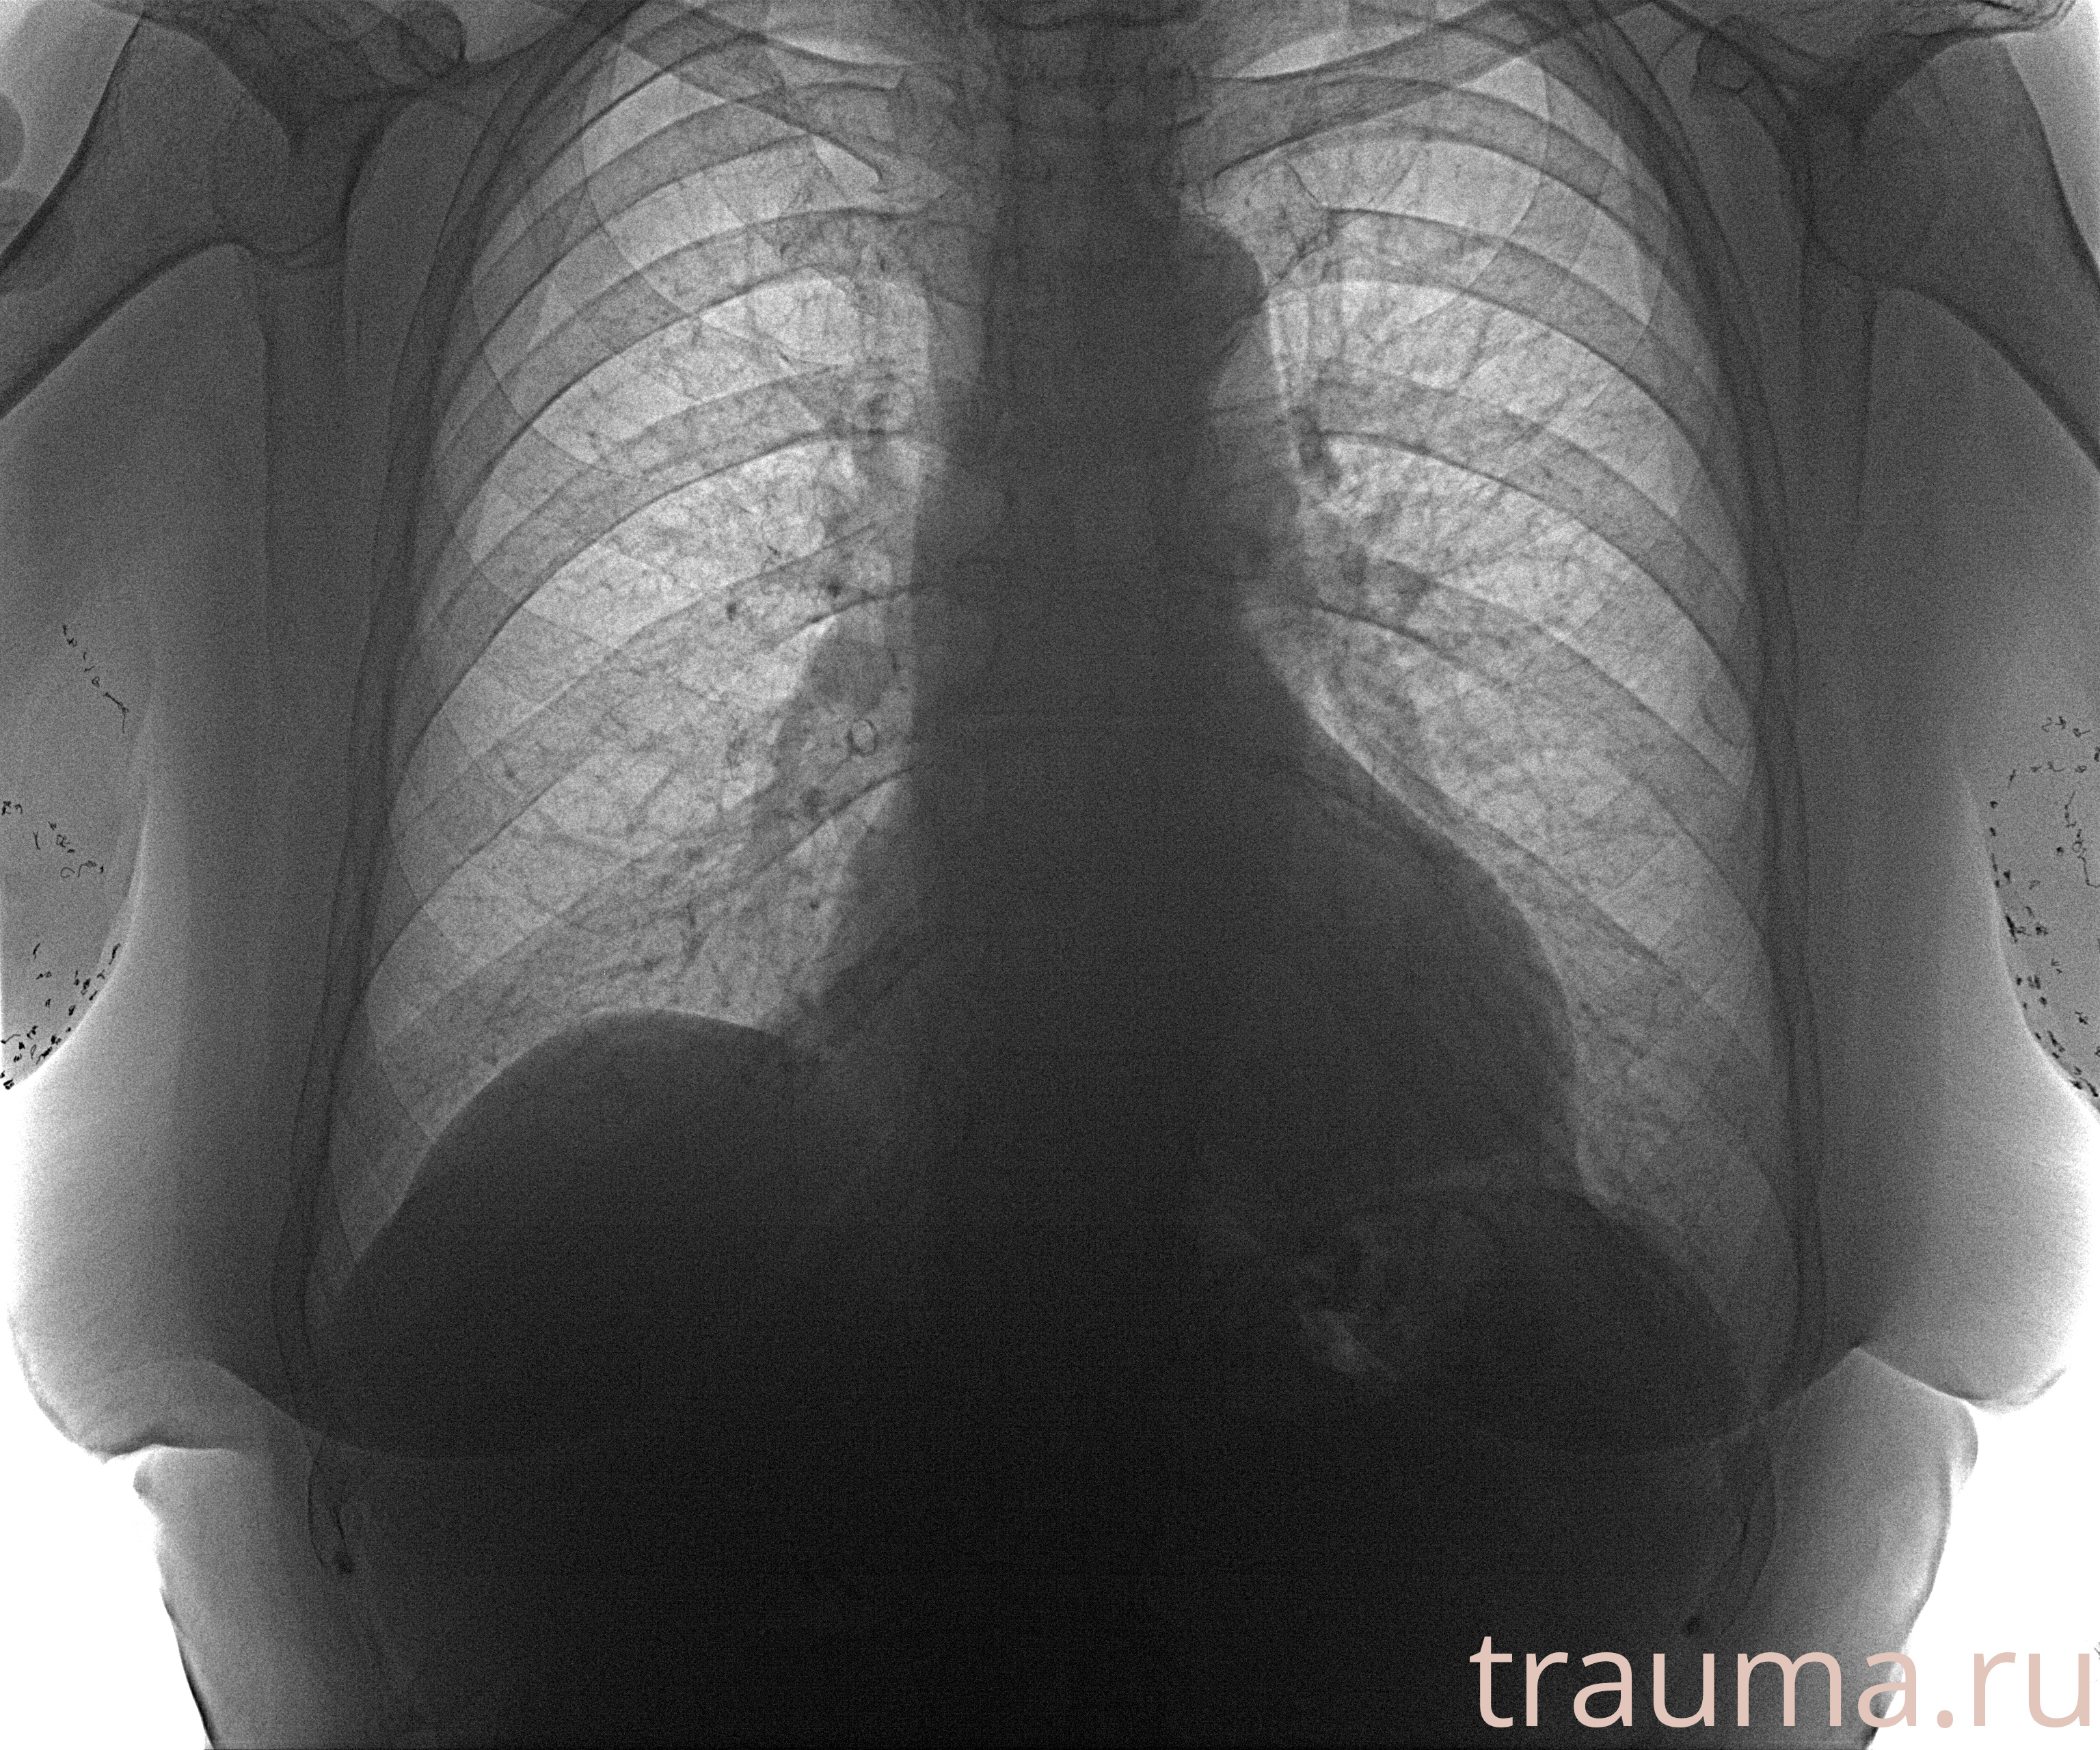

Рентген на дому: по вашему адресу приезжает врач-рентгенолог, травматолог-ортопед с мобильным рентгеновским аппаратом, проводит диагностику травмы или заболевания, делает необходимые рентгенограммы, дает рекомендации по дальнейшему лечению. Получить качественные снимки в домашних условиях возможно благодаря уникальной методике, разработанной МосРентген Центром для института  Склифосовского